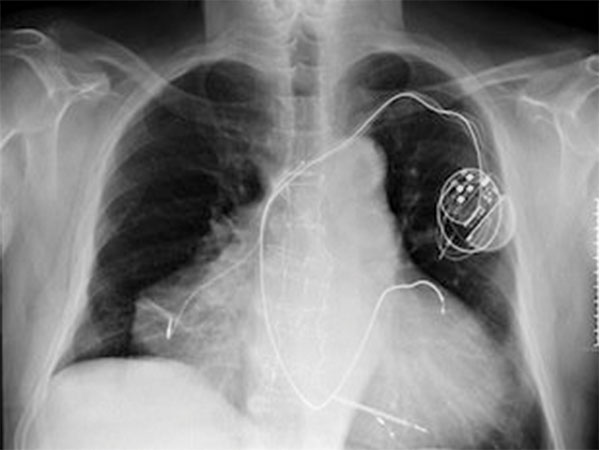

இரு இதயங்களுடன் ஒரு மனிதன்

இத்தாலியைச் சேர்ந்த ஒருவர் பிறக்கும் போது சாதாரணமாக தான் இருந்தார். ஒருமுறை இவருக்கு மாரடைப்பு வந்தது. இவரை மருத்துவரிடம் அழைத்து சென்று பரிசோதித்த போது இவருக்கு இரு இதயங்கள் இருப்பது தெரிய வந்தது. நல்ல வேளை ஒரே சமயத்தில் இரு மாரடைப்பைத் தாங்கிய இவர் தற்போது சந்தோஷமாக வாழ்ந்து வருகிறார்.